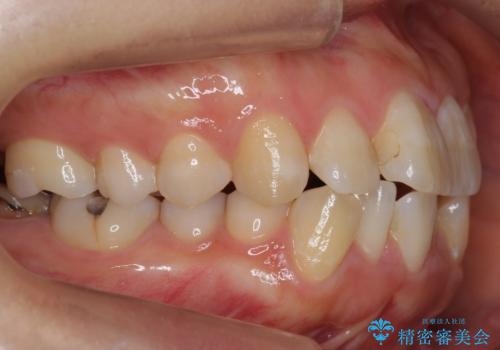

- 歯並びを主訴に来院。

左上2番は以前抜歯したとのこと。

奥歯を後ろに下げて、前歯を並べています。

マウスピースと矯正用のミニスクリューを使用して治療しています。

右下7は根管治療をおすすめしましたが、患者様のご希望により抜歯となり、そのスペースを利用して下の前歯をならべています。